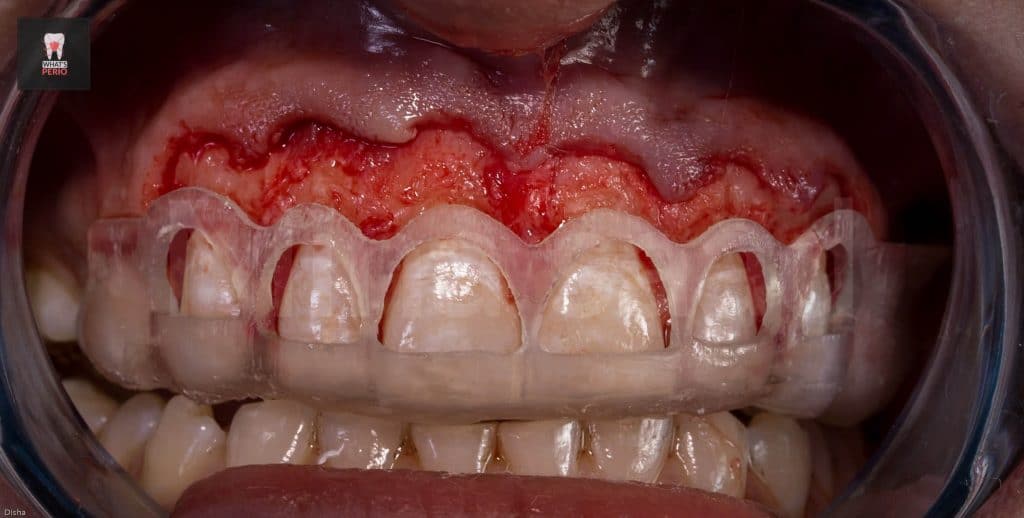

-External bevel gingivectomy was made while the guide in place.

-Ostectomy was made using a rose head diamond stone then the guide was put in place again & it was observed that the apical level & the alveolar crest is at the same level now.

-Osteoplasty wass performed to reshape the prominent canine eminence to be in harmony with the left one & in general the labial plate of bone was shaped & any sharp angles resulting from ostectomy procedure were removed for better adaptation of the flap ensuring nice healing results.

-The flap was sutured using single sling sutures. “4/0 Vicryl sutures” “resorbable”

-The patient is recalled after 4 weeks & it was observed that the gummy smile was decreased & the patient was very satisfied with the result & decided to postpone the 2nd step.